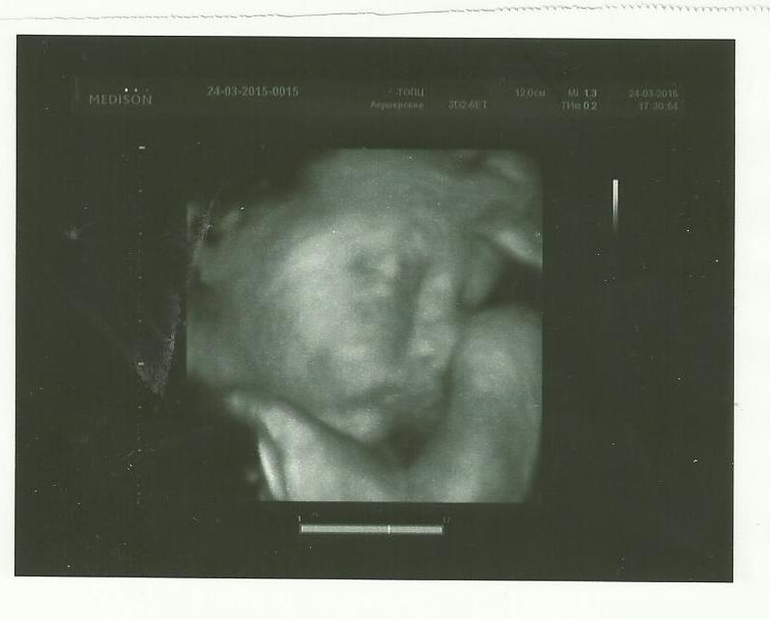

Наше фото в 3D на третьем скрининге.

32 неделя идет.

Как здорово что уже можно увидеть личико и четко представлять себе с кем ты разговариваешь. По-тихоньку готовлюсь к родам, начинается инстинкт гнездования, он уже давно начался, но сейчас обостряется, хочется по быстрее уже все доделать, закупить, перестирать собрать чтоб все стояло готовое. И хоть на третьем скрининге меня напугали амниотическими тяжами, я перестала об этом переживать и думаю что все у нас будет ХОРОШО!

хорошенькие вы)) а это что ножка возле головы?

Это 2 ручки одна вверху, другая внизу, они не вошли полностью.